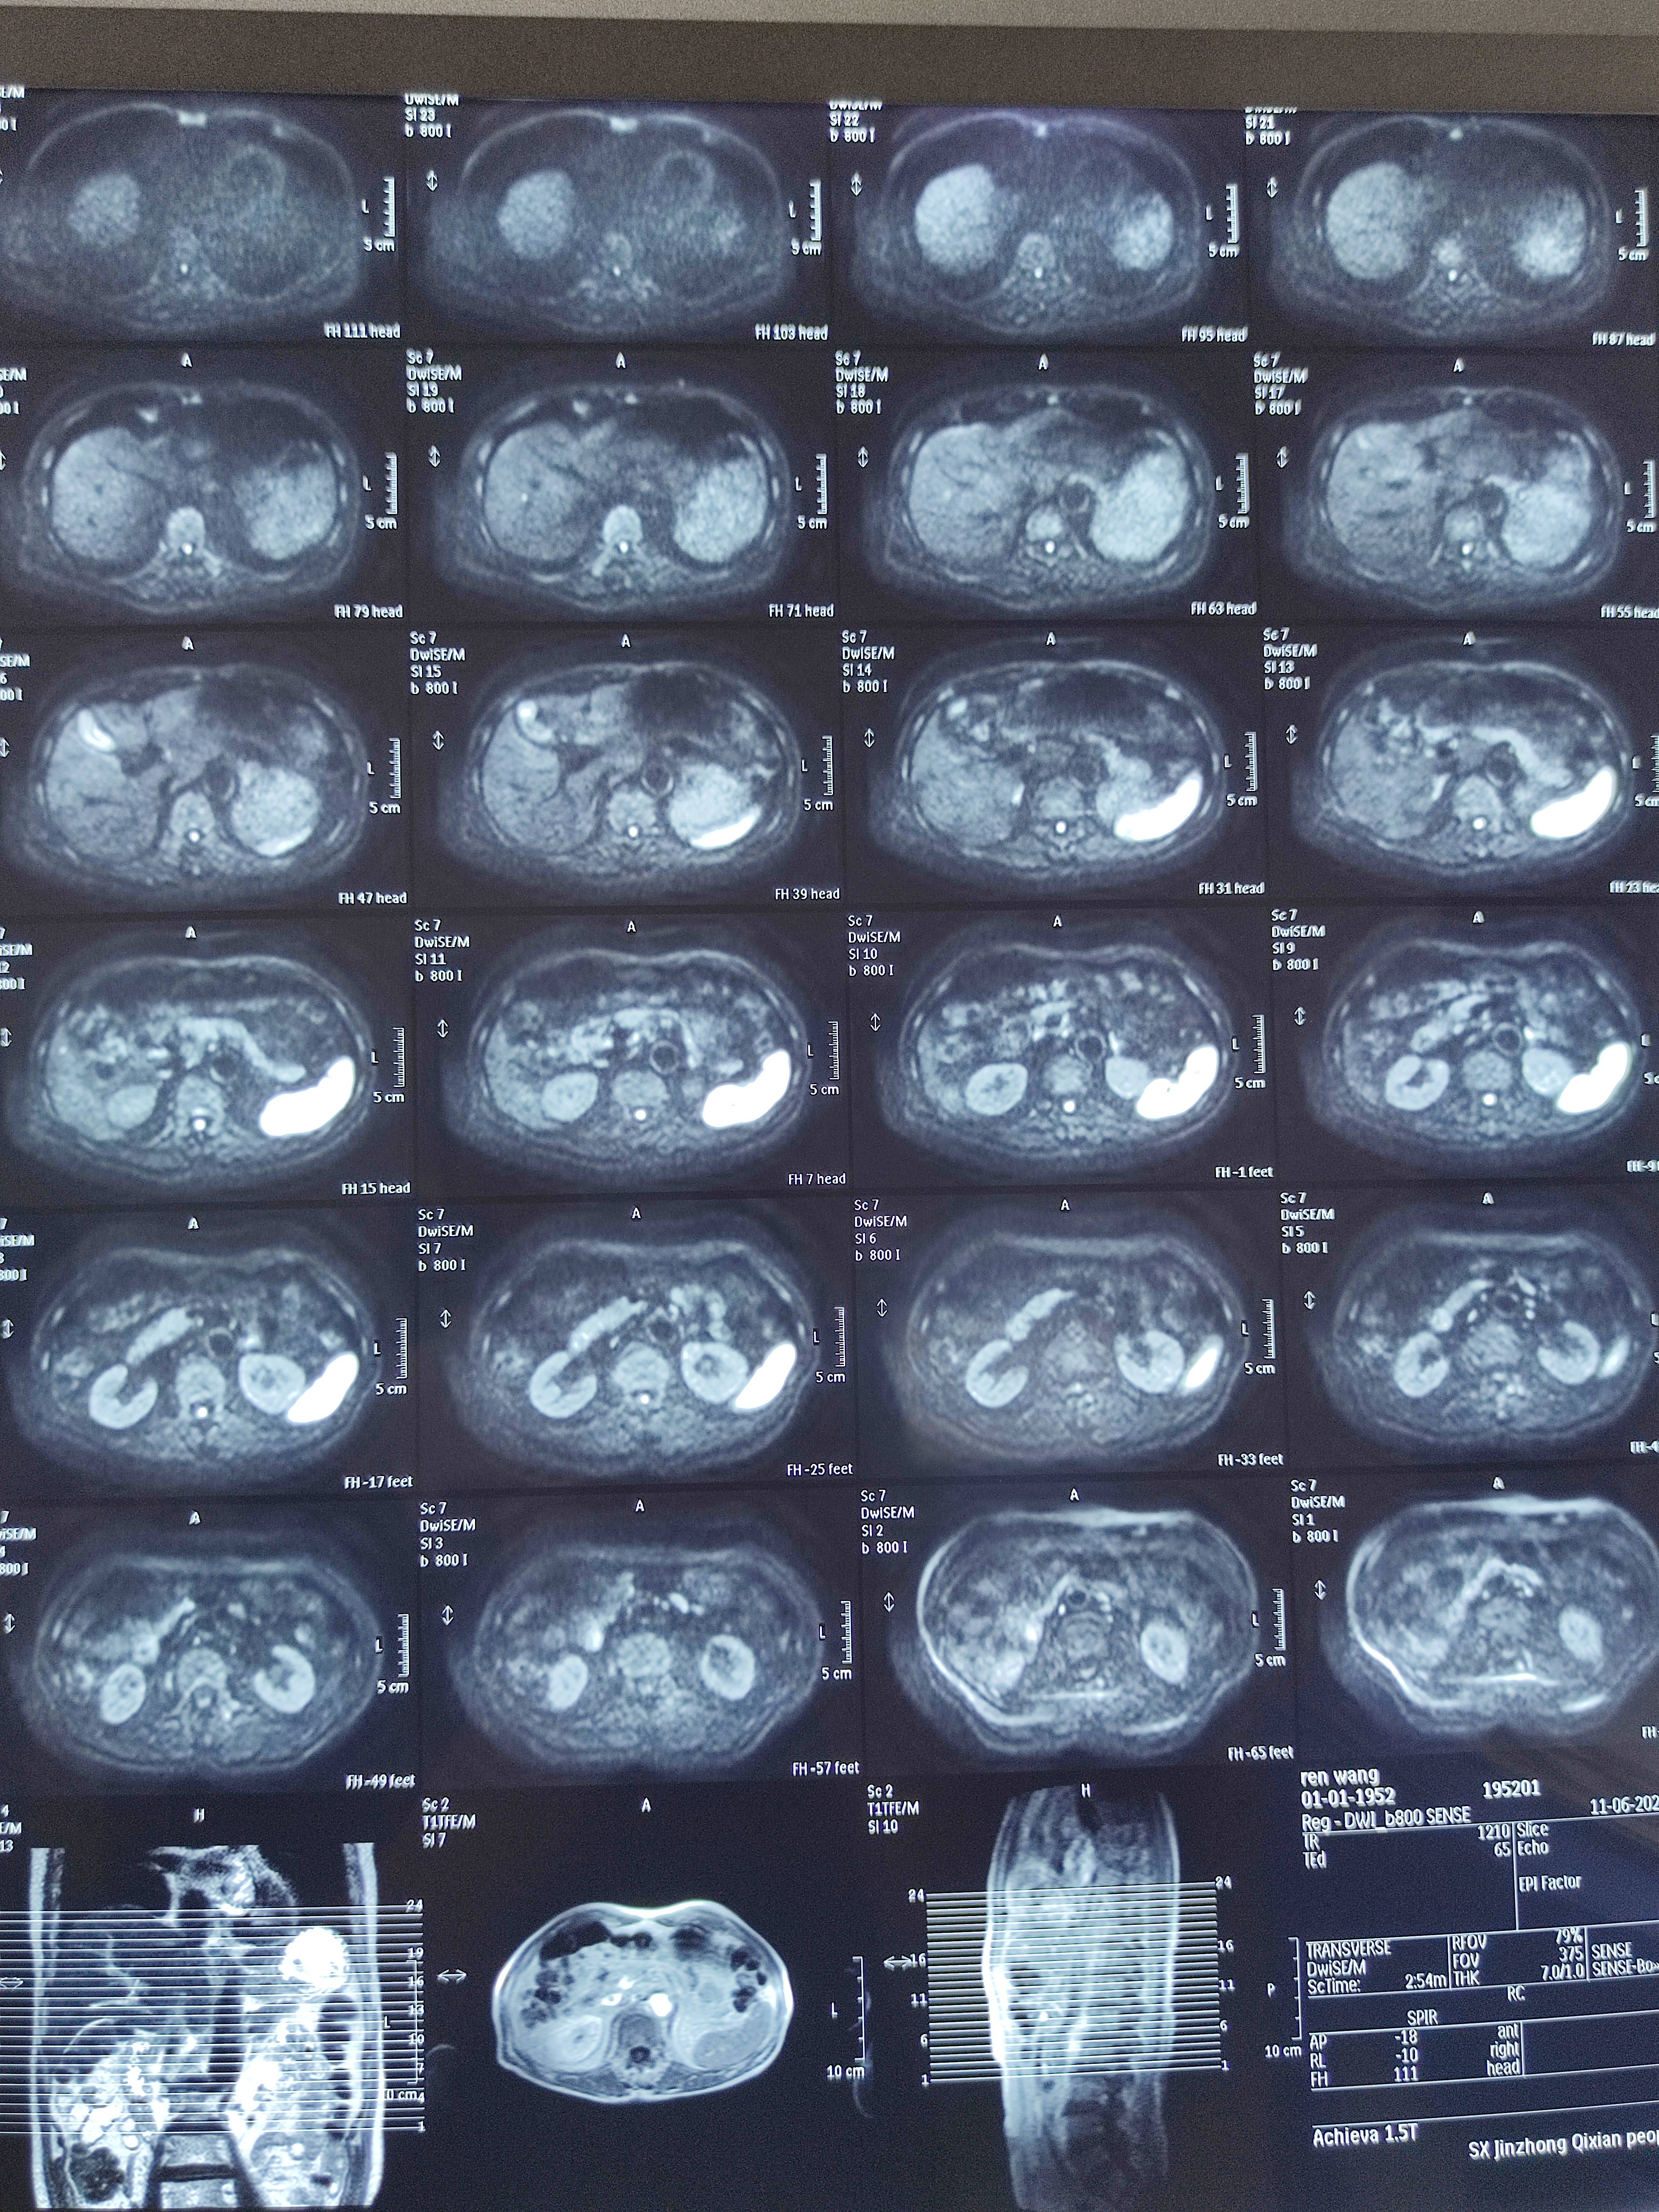

四月份癌胚抗原还是5.6,这个月到8了,持续升高。做了核磁增强,左侧桥小脑角哪有个地方不确定。肝脏核磁平扫弥散有两个点状高信号,转移也排不了,胃肠镜正常,左颈部有个变圆的淋巴结,保险点是不该加个化疗药了?咨询了陈波主任,等结果的吧!图片